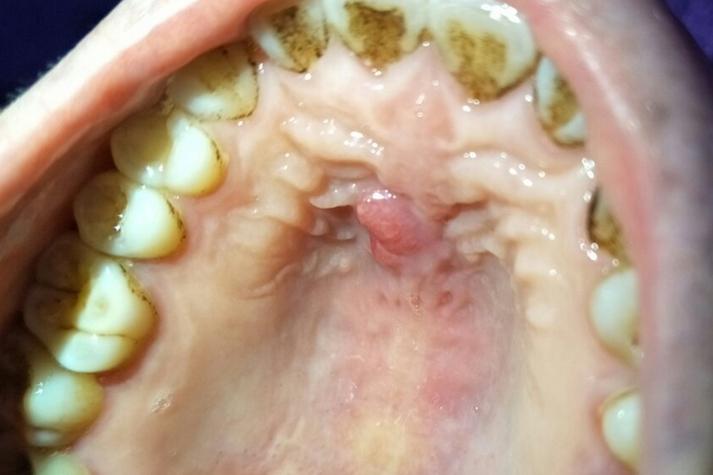

智齿冠周炎

如果您的肿胀是在口腔最后方、靠近下颌骨的位置,那很可能是智齿(尤其是阻生智齿)引起的。

- 症状:智齿周围牙龈红肿、疼痛,甚至有脓液溢出,张口受限,吞咽困难,可能伴有同侧面颊部的肿胀,严重时会导致张嘴困难,甚至发烧。

- 原因:智齿没有完全长出,牙龈瓣覆盖在牙齿上,食物残渣和细菌堆积导致感染。